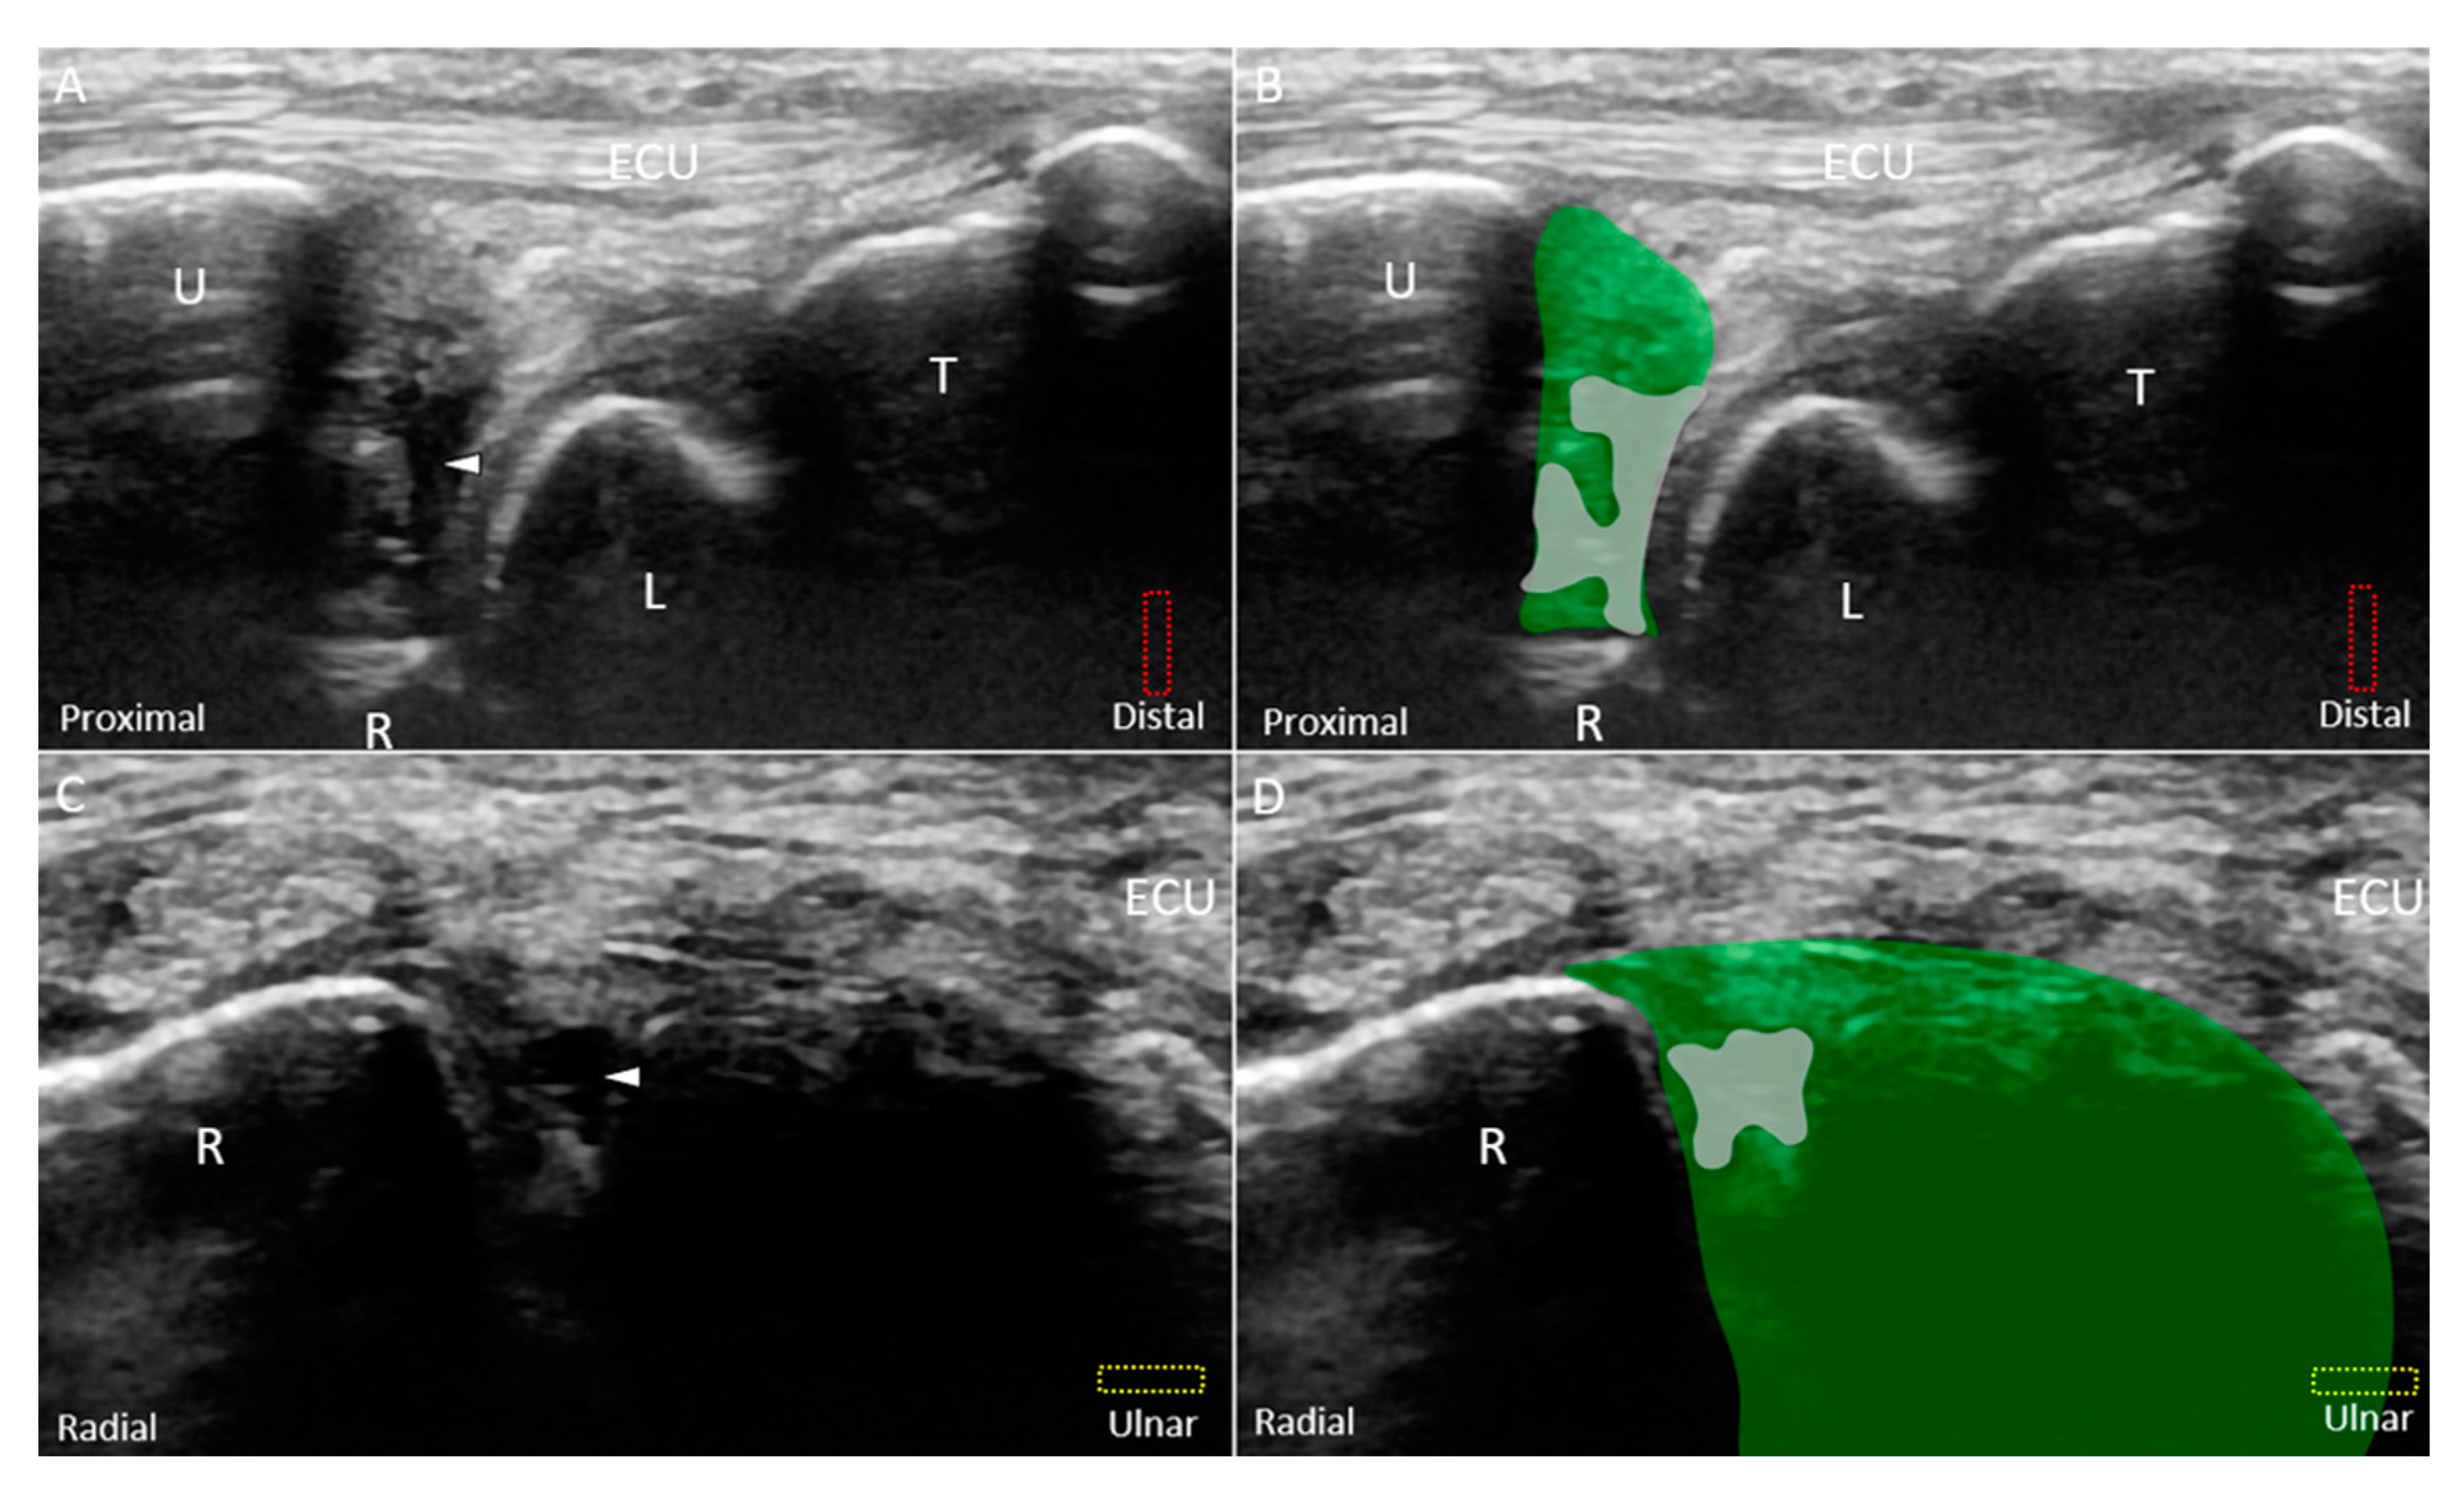

6. US Imaging

6.1. Scanning Protocol

7. Pathologies—Classification

8.2. US-Guided Injection